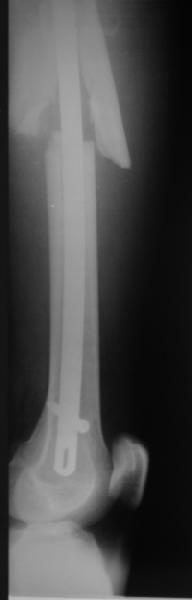

Мы бы не стали открывать, такие переломы срастаются, хотя бы и с краевым дефектом. То есть если удалять стержень потом, то сильно попозже обычного. В приложении пример. Сразу после операции и через 11 мес. Понятное дело, пациент к тому времени давно и не хромал, и функция колена была полная.